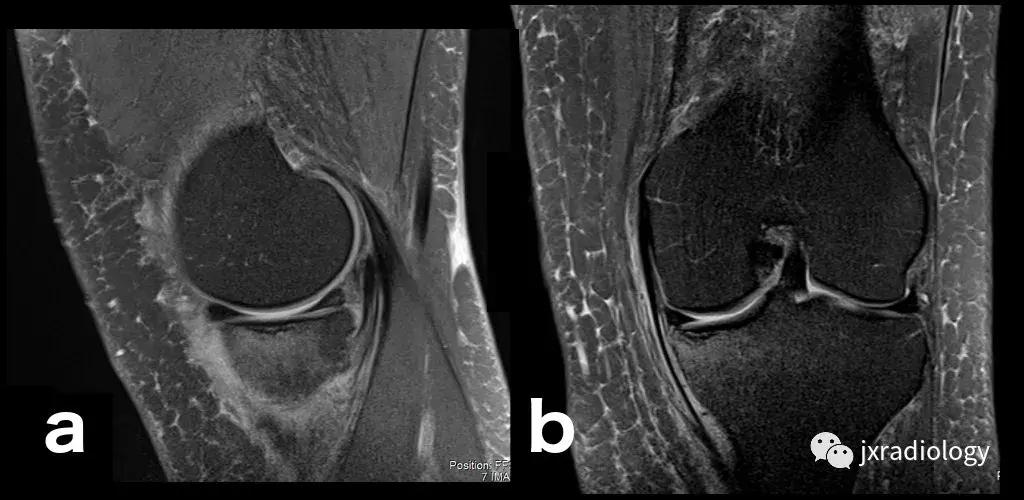

图28:正常的红骨髓:这是寻找骨髓水肿时可能出现的误区。造血系统红骨髓(由于年轻患者正常分布或成人骨髓再生)在T1-WI(b)和水敏序列(a:PD-FS-WI)上均具有中等信号强度。T1-WI上的正常红骨髓相对于肌肉的分布(通常在干骺端)的特征性模式和较高的信号强度(与T1-WI上肌肉组织的等信号或低信号的病理性骨髓相反),应能及时发现这一正常发现。